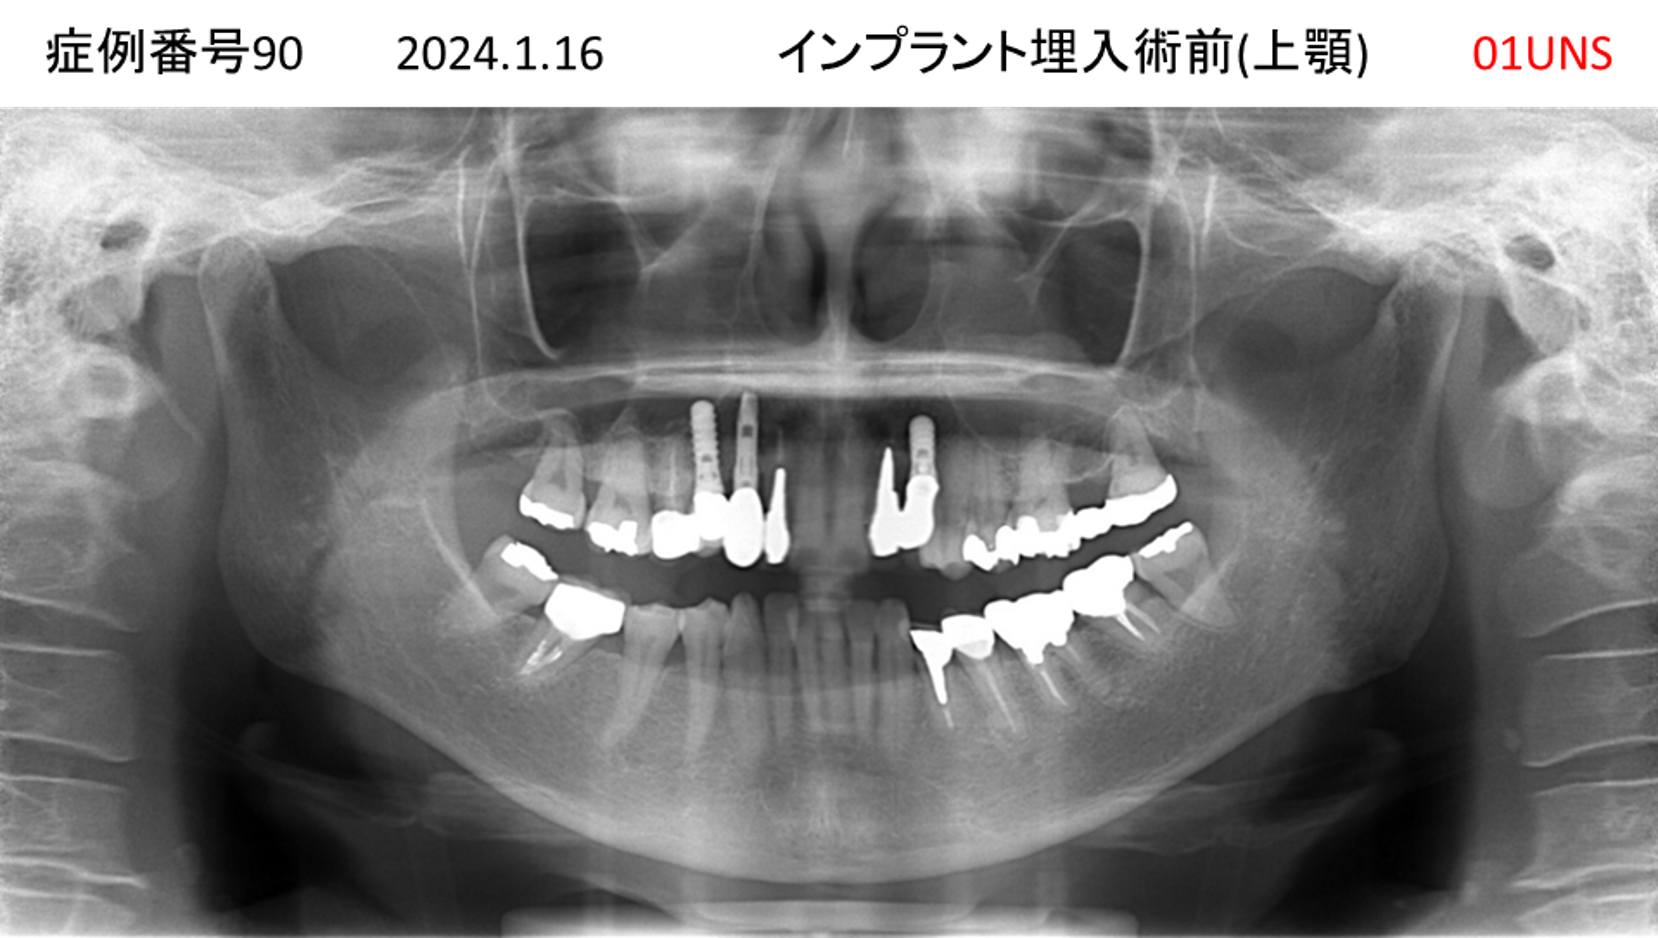

上の前歯が揺れてきてかめない患者様のインプラント症例

| 治療名称 |

インプラント |

| 治療費用 |

440万円+税 |

| 治療期間 |

6か月 |

| 患者さんの症状(主訴) |

上の前歯が揺れてきた。かめない |

| 治療内容 |

サイナスリフト、GBR、インプラント、即時荷重 |

| 治療結果 |

上の前歯の揺れが収まった。奥歯でしっかり噛める。 |

| 治療の注意点(リスク/副作用) |

インプラントが壊れたら再治療が必要 |